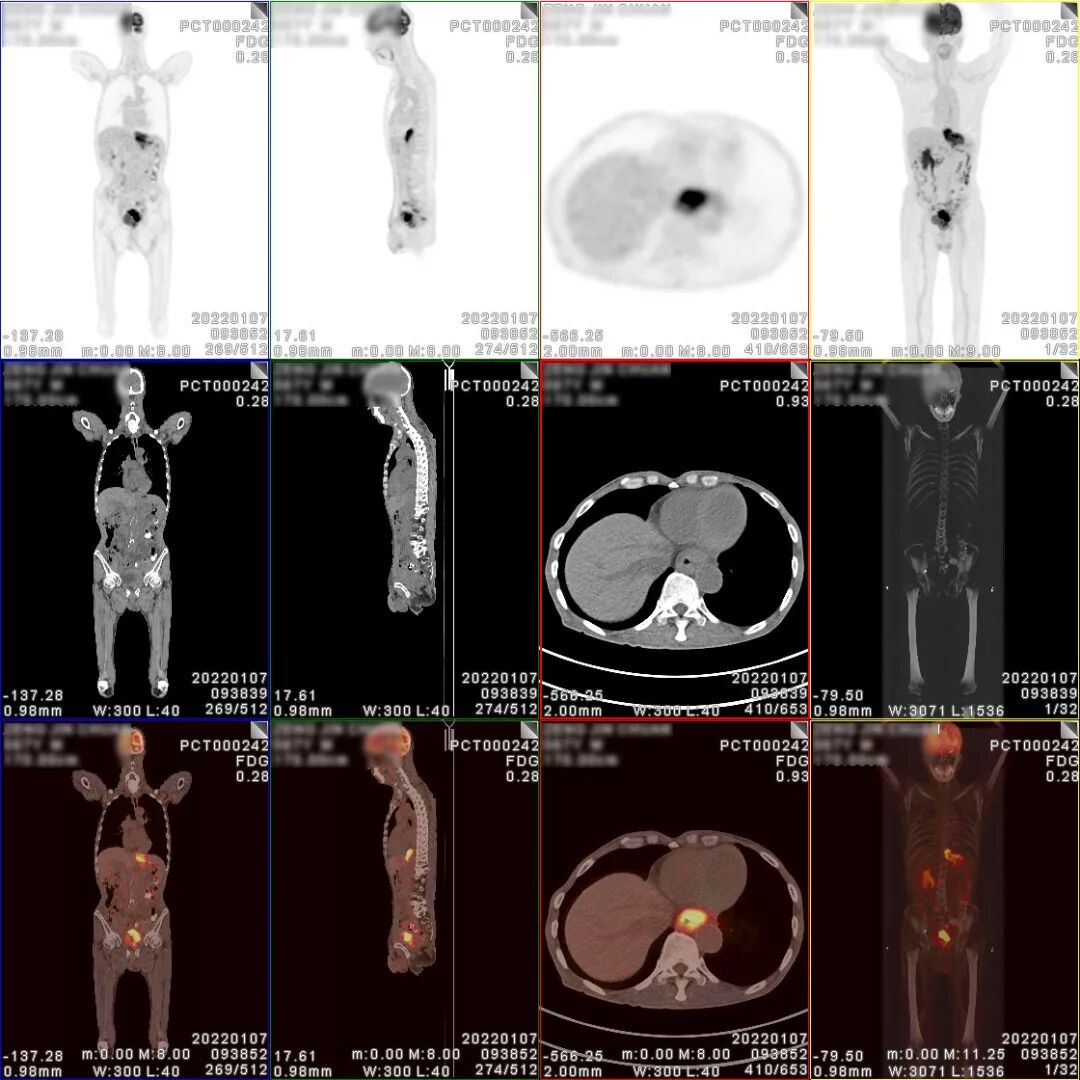

18F-FDG PET/CT检查图像

胃癌术后、化疗后,胃术后缺如,CT 见食管下段与肠道吻合口区软组织明显增 厚,密度较均匀,边缘欠清,PET 于相应部位可见不规则形放射性异常浓聚影,大小 约 71×27×63mm,SUVmax 为 9.5。CT 于左下腹部肠系膜上可见结节状密度增高影, 大小约 14×8mm,密度较均匀,边缘欠清,PET 于相应部位可见结节状放射性异常浓 聚影,SUVmax 为 4.9。CT 见腹盆腔其他部位肠系膜密度稍增高,边缘模糊,PET 于 相应部位未见明显放射性异常浓聚影。CT 见膀胱顶壁、左侧壁、左后壁及膀胱三角 区软组织明显增厚,密度较均匀,边缘欠清,堵塞双侧输尿管下段膀胱入口,并向 下与前列腺分界不清,PET 于增厚的膀胱壁内可见不规则形放射性异常浓聚影,大小约80×34×47mm,SUVmax 为 30.3;CT 见前列腺体积不大,其内可见多个小斑点状 高密度钙化影,PET 于前列腺内可见块状放射性异常浓聚影,大小约 39×36×35mm, SUVmax 为 6.9。CT 于盆腔内右侧髂外血管旁可见稍肿大淋巴结,大小约 10×7mm, PET 于相应部位可见结节状放射性异常浓聚影,SUVmax 为 2.9。

PET/CT诊断:

1、胃癌术后、化疗后,食管下段与肠道吻合口区软组织明显增厚,代谢增高, 考虑肿瘤复发病灶;

2、膀胱顶壁、左侧壁、左后壁及膀胱三角区不规则形代谢增高影及前列腺内块 状代谢增高影,考虑膀胱癌并侵犯前列腺;

3、左下腹部肠系膜上结节状密度增高影,代谢增高,考虑转移灶;腹盆腔其他 部位肠系膜密度稍增高,未见代谢增高,请结合临床追踪复查以排外低代谢腹膜 转移灶的可能;

4、盆腔内右侧髂外血管旁稍肿大淋巴结,代谢稍增高,不排外淋巴结转移灶的可能。